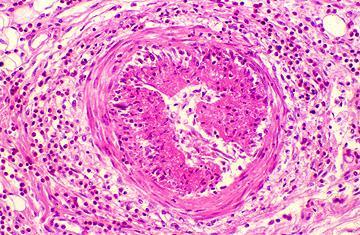

1. Poliarteritis nodosa

1. Necrosis fibrinoide

1. Daño

1. Riñón

1. Músculo

1. Piel

1. Sistema Nervioso Periférico

1. Tubo digestivo

2. Hepatitis B

1. Púrpura palpable

1. Aneurismas